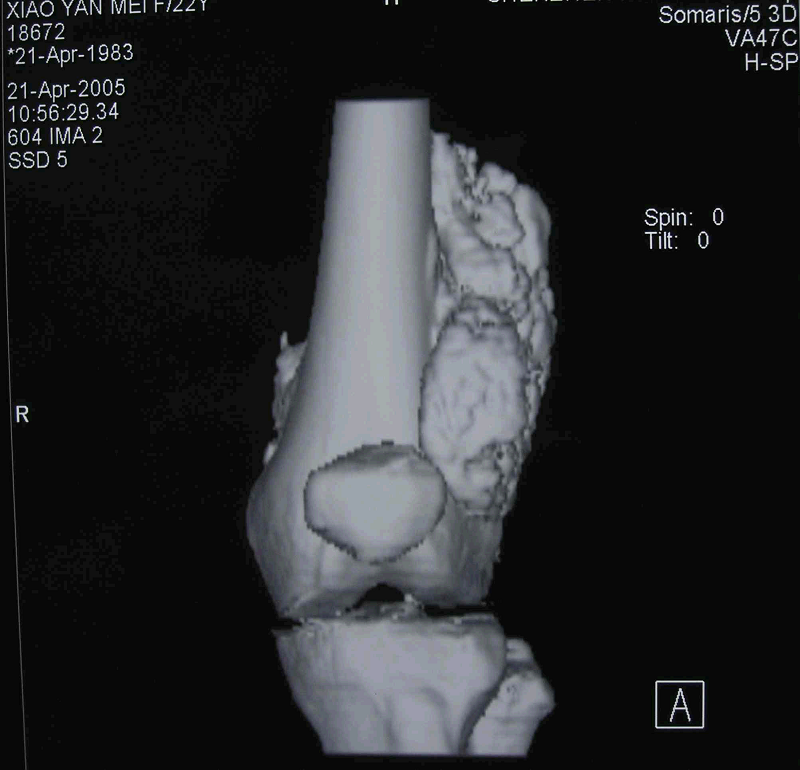

图 15 术前CT三维重建象

图 16术前MRI